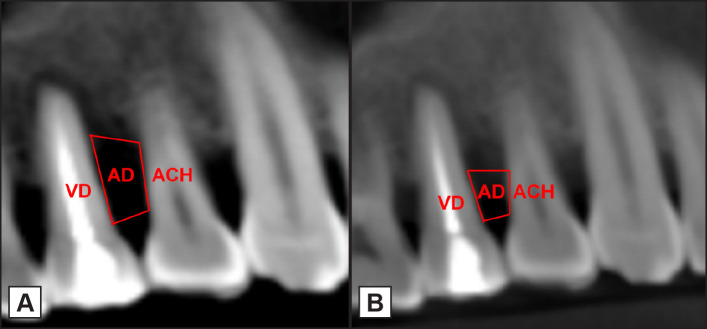

Material and methods: Thirty intrabony defects in 14 patients were treated with autologous platelet-rich fibrin with open flap debridement. Clinical and radiographic parameters were recorded at baseline and 9 months postsurgery. Gingival crevicular fluid (GCF) was collected prior to the surgery, 3 months, 6 months and 9 months postsurgery and was analysed for levels of osteocalcin using ELISA.

Results: All the clinical and radiographic parameters like plaque index (2.41 to 1.38) and gingival index (2.37 to 1.4) scores, probing pocket dept (6.43 to 3.78 mm), clinical attachment level (7.25 to 4.61 mm), relative attachment level (10.35 to 7.42 mm) and vertical depth (7.46 to 4.9), alveolar crest height (6.2 to 5.9), area of the defect (17.8 to 14.5) respectively showed improvement which was statistically significant (P < 0.001) except for the defect width (8.86 to 8.77) with P = 0.39. A moderate negative correlation was established between the GCF osteoclcin levels and the clinical and radiographic parameters at baseline and 9 months except for the % of defect fill which showed moderate positive correlation at 9 months (r = 0.55, P = 0.002).